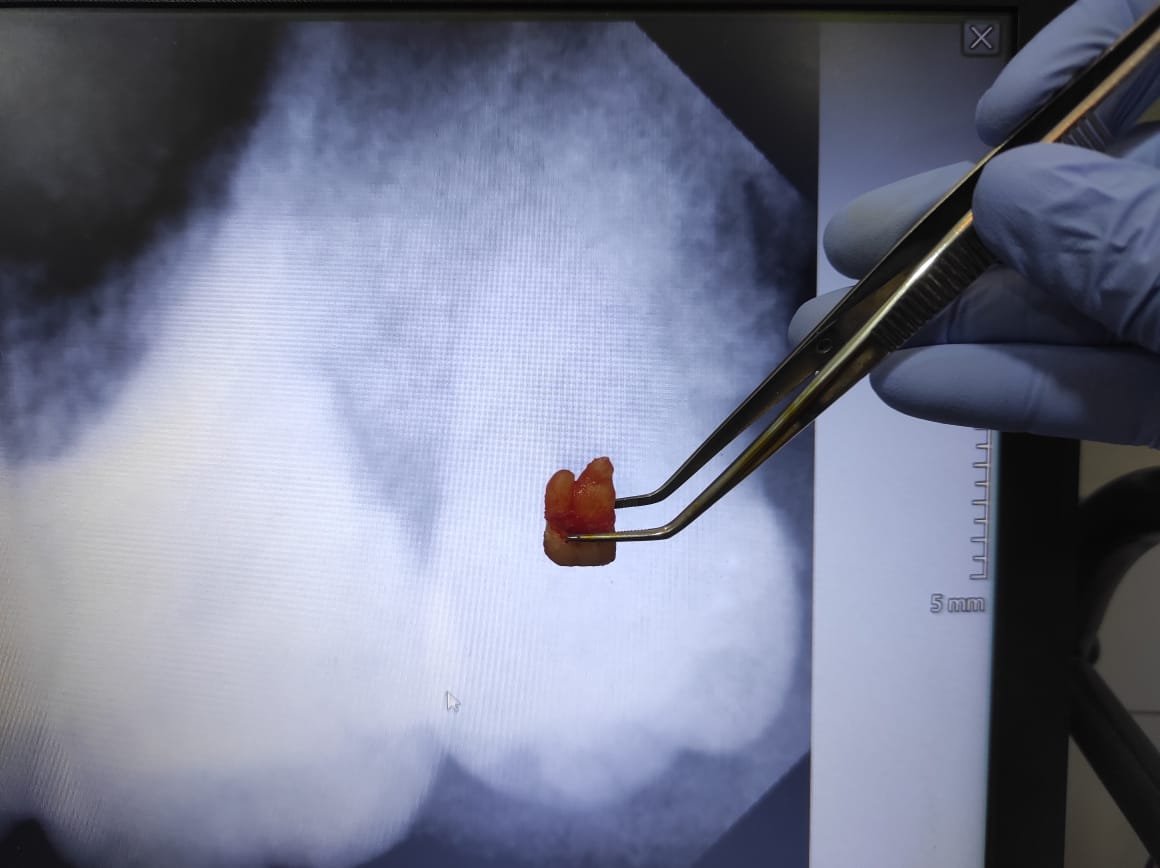

4. Pengangkatan gigi

Bila gigi sulit dicabut, dokter membaginya menjadi beberapa bagian lalu mengangkat potongan satu per satu.

After dari Cabut Gigi Bungsu